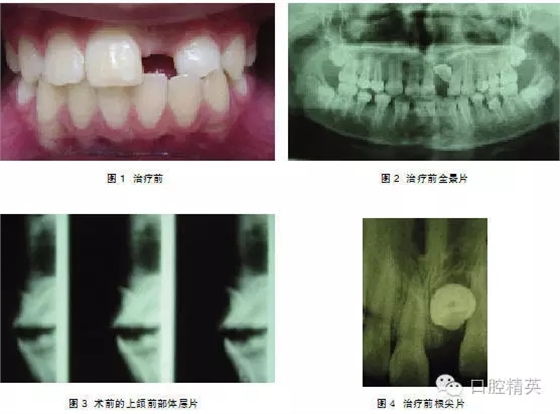

典型病例1: 患者,男,10歲,因左上前門牙未萌出于2009年10月來上海第九人民醫(yī)院預(yù)防、兒童口腔科就診。檢查: |1未萌,1| 全萌,1|2之間間隙為4mm。牙片及全景片示: |1骨內(nèi)埋伏,1| 2之間有埋伏多生牙,多生牙與 |1的重疊,不能清晰顯示多生牙和 |1在頜骨中的具體方位及相關(guān)關(guān)系(圖1-2),采用CBCT掃描后,圖像能清晰顯示多生牙和 |1的形態(tài)、大小、數(shù)目、牙根發(fā)育情況、在頜骨中具體位置、萌出方向及相互關(guān)系(圖3-4),經(jīng)手術(shù)證實情況與CBCT圖像顯示完全一致,手術(shù)拔除多生牙, |1作外科開窗術(shù)+正畸牽引治療。

典型病例2:患者,女,10歲,因1|未萌來我院就診(圖1)。

檢查:1|未萌, |1全萌, 2|1之間間隙為5mm。X線示:1| 骨內(nèi)埋伏,倒置,牙冠的舌側(cè)向外,彎根。 |1牙根已形成。(圖2、3)。

處理:2004年3月行外科開窗+正畸牽引治療,7個月后檢查:1|已萌出,未完全到位,1|唇側(cè)牙根處稍隆起,即為彎曲的牙根。因1|為彎根比較嚴重,如完全排齊有可能使牙根暴露,故未完全排齊(圖4、5)。

典型病例3:患者,男,11歲,因—1未萌來我院就診(圖1)。

檢查: |1未萌,1|全萌,1|2之間間隙為5mm。X線片示: |1骨內(nèi)埋伏,倒置,埋伏牙倒置角度在130°,牙冠的腭側(cè)面向外,稍彎根,1| 牙根基本形成(圖2~4)。

處理:行外科開窗+正畸牽引治療,6個月后破齦萌出,連續(xù)牽引,12個月后到位(圖5~7)。